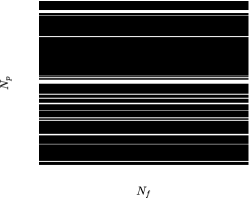

MRI data ( denotes the set of all complex-valued numbers) are observed in k-space (frequency domain), which spans an area of size (cf. Figs. 1a and 1b), with standing for the number of phase-encoding lines and for the number of frequency-encoding ones [1]. Data can be considered as the two-dimensional (discrete) Fourier transform of the image-domain data , i.e., [1]. Without any loss of generality, this study assumes that the “low-frequency” part of is located around the center of the area. Availability of the data over the whole k-space is infeasible in practice; k-space is usually severely under-sampled [3]. There exist several strategies to sample the k-space; examples are the 1-D Cartesian (Fig. 1a) and the radial (Fig. 1b) ones, where the “white” lines in Figs. 1a and 1b denote the available/sampled data, while data in the “black” areas are not observed. A general trend among sampling strategies is to put more emphasis on low-frequency components, which carry contrast information and with high SNR, and select few high-frequency components, which comprise high-resolution image details. The 1-D Cartesian sampling pattern emulates the acquisition of k-space pixels via the 1-D Gaussian distribution, acquiring a large number of samples in the central k-space area while sampling few ones from the “high-frequency” area (cf. Fig. 1a). The radial-sampling pattern consists of radial spokes which yield dense sampling at the center of k-space, while the sampling density is decreased as the spokes move away from the center (cf. Fig. 1b).

The proposed framework is validated over a range of undersampling/acceleration rates, defined by . 1-D Cartesian (Fig. 1a) as well as radial (Fig. 1b) sampling were applied to both the phantom datasets. To save space, only the 1-D Cartesian-sampling results are demonstrated for the MRXCAT dataset, while radial-sampling ones are shown for the phantom generated using real MR scans. Nevertheless, BiLMDM’s performance against the competing reconstruction algorithms follows a similar trend also for sampling strategies not included in the manuscript due to space limitations.